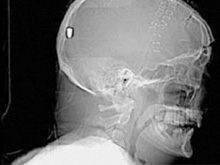

В Британии врачи нашли у пациента пулю в голове13.05.10 13:07 Прочтений новости 1046 Общество В Британии у пациента, который поступил в клинику с подозрением на инсульт, врачи обнаружили пулю в голове. Но остается неизвестным, как мужчина получил ранение.Рентгеновские снимки головы показали, что в полости черепа находится инородный предмет. Мужчине сделали томографию головы, и врачи установили, что этим предметом является пуля. Как сообщается, 19 апреля 61-летний Питер Хесфорд упал во время работы у себя в саду. Позже его обнаружила жена, которая вызвала скорую. Мужчина оставался в сознании, но не мог говорить. Медики, прибывшие на место, заподозрили у Питера Хесфорда инсульт и доставили его в Больницу Уитеншо. Эксперты по баллистике, изучив снимки пациента, пришли к выводу, что пуля, застрявшая в затылочной области, могла попасть туда через глаз. Но мужчина не помнит, что именно с ним произошло. Врачи попытались удалить пулю, однако это оказалось невозможным из-за ее положения по отношению к окружающим структурам. Пациент остается в больнице, а его состояние расценивается как стабильное. Комментарии (всего 0)